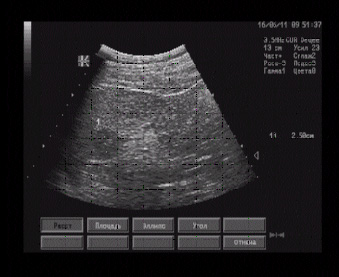

Правая почка визуализируется на уровне подвздошной кос ти справа, размерами 93 х 43 мм, форма типичная, почка ротирована, контуры волнистые, паренхима толщиной 18 - 22 мм, однородная, равномерно гипоэхогенная, кортико-медуллярная дифференцировка умеренно выражена, ЧЛС расширена до 12 мм, просвет свободен.

Левая почка лоцируется позади мочевого пузыря слева, ротирована, размерами 92 х 42 мм, форма типичная, контуры волнистые, паренхима толщиной 18 - 21 мм, однородная, равномерно гипоэхогенная, кортико-медуллярная дифференцировка умеренно выражена, ЧЛС расширена до 12 мм.

Эхографические признаки тазовой дистопии левой почки и пояснично-подвздошной дистопии правой почки.